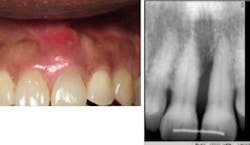

Case No. 1 — Mrs. High Anxiety

A 67-year-old African American female presented in 2001. Her diagnosis was chronic periodontitis and diabetes. Fear and anxiety resulted in refusal of osseous surgical care for bone regeneration and pocket reduction. Scaling was performed and the patient did not return for five years. She then presented with an abscess on No. 9 with significant bone loss that was not evident five years ago. Tooth No. 9 tested vital. The patient accepted the LANAP protocol. Treatment was done in January 2012.

Mrs. High Anxiety before the LANAP protocol.

Mrs. High Anxiety has returned for all postop appointments this time around. Her abscess has resolved and a small amount of bone regeneration is noted on the eight-month postop radiograph. If the bone fill is not better at one year, a retreatment of the site will be suggested. Tissue height, which was a major esthetic concern, has remained at an acceptable level for the patient.

Mrs. High Anxiety after treatment.